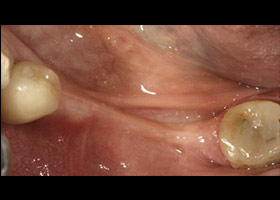

proimages/case/Artificial_implant/Horny3.jpg

移植後牙齦成功生長再生